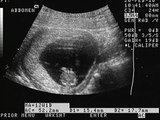

¿En qué ayuda un ultrasonido entre las semanas 11-13.6 del embarazo por un médico materno fetal?

De la mano de un médico, te daremos a conocer información muy interesante. De las dudas que normalmente tenemos, te daremos a conocer respuestas directamente de expertos en el tema.